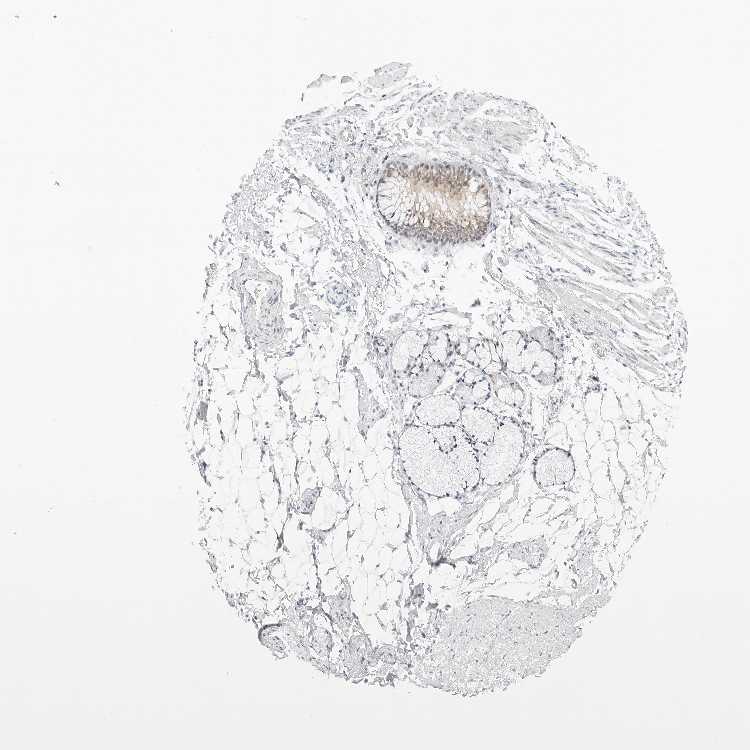

TISSUE PRIMARY DATA SOFT TISSUE Show tissue menu

SOFT TISSUE - Expression summary

SOFT TISSUE 1 - Antibody stainingi

Antibody staining in the annotated cell types in the current human tissue is reported as not detected, low, medium, or high, based on conventional immunohistochemistry profiling in selected tissues. This score is based on the combination of the staining intensity and fraction of stained cells.

Each image is clickable and will lead to virtual microscopy that enables deeper exploration of all samples and also displays staining intensity scores, fraction scores and subcellular localization as well as patient and tissue information for each sample.

Antibody HPA027120Antibody HPA027125Antibody HPA027268

Fibroblasts Not detectedNot detectedNot detected

Peripheral nerve Not detectedNot detectedNot detected

SOFT TISSUE 2 - Antibody stainingi